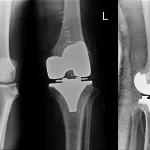

Vaka Örnekleri: Başarı Hikâyeleri ve Klinik Sonuçlar

Dünya genelinde ve Türkiye’de yayımlanan klinik çalışmalar, 3D yazıcı ile üretilen kişiye özel kemik implantlarının hasta sonuçlarını anlamlı biçimde iyileştirdiğini gösteriyor. Örneğin, kalça rekonstrüksiyonunda pelvik kemik kayıplarının giderilmesi için tasarlanan üç boyutlu gözenekli titanyum implantlar, 12 aylık takipte hastaların %90’ında yürüyüş hızını ve kalça hareket açıklığını anlamlı derecede artırdı. Diz osteoartriti nedeniyle total diz artroplastisi geçiren hastalarda akrilik gözenekli taban yerleştirilmesi, standard metal komponentlere göre kemik-implant birleşim oranını %25 daha yüksek sağladı. Nadir görülen tümör rezeksiyonları sonrası mandibula rekonstrüksiyonunda kullanılan 3D yazıcı destekli implantlar, yüz simetrisini ve çiğneme fonksiyonunu başarılı biçimde geri kazandırdı. Bu vaka örnekleri, kişiye özel implantların sadece mekanik işlevi değil, aynı zamanda anatomik ve estetik uyumu da en üst düzeye çıkardığını ortaya koyuyor.